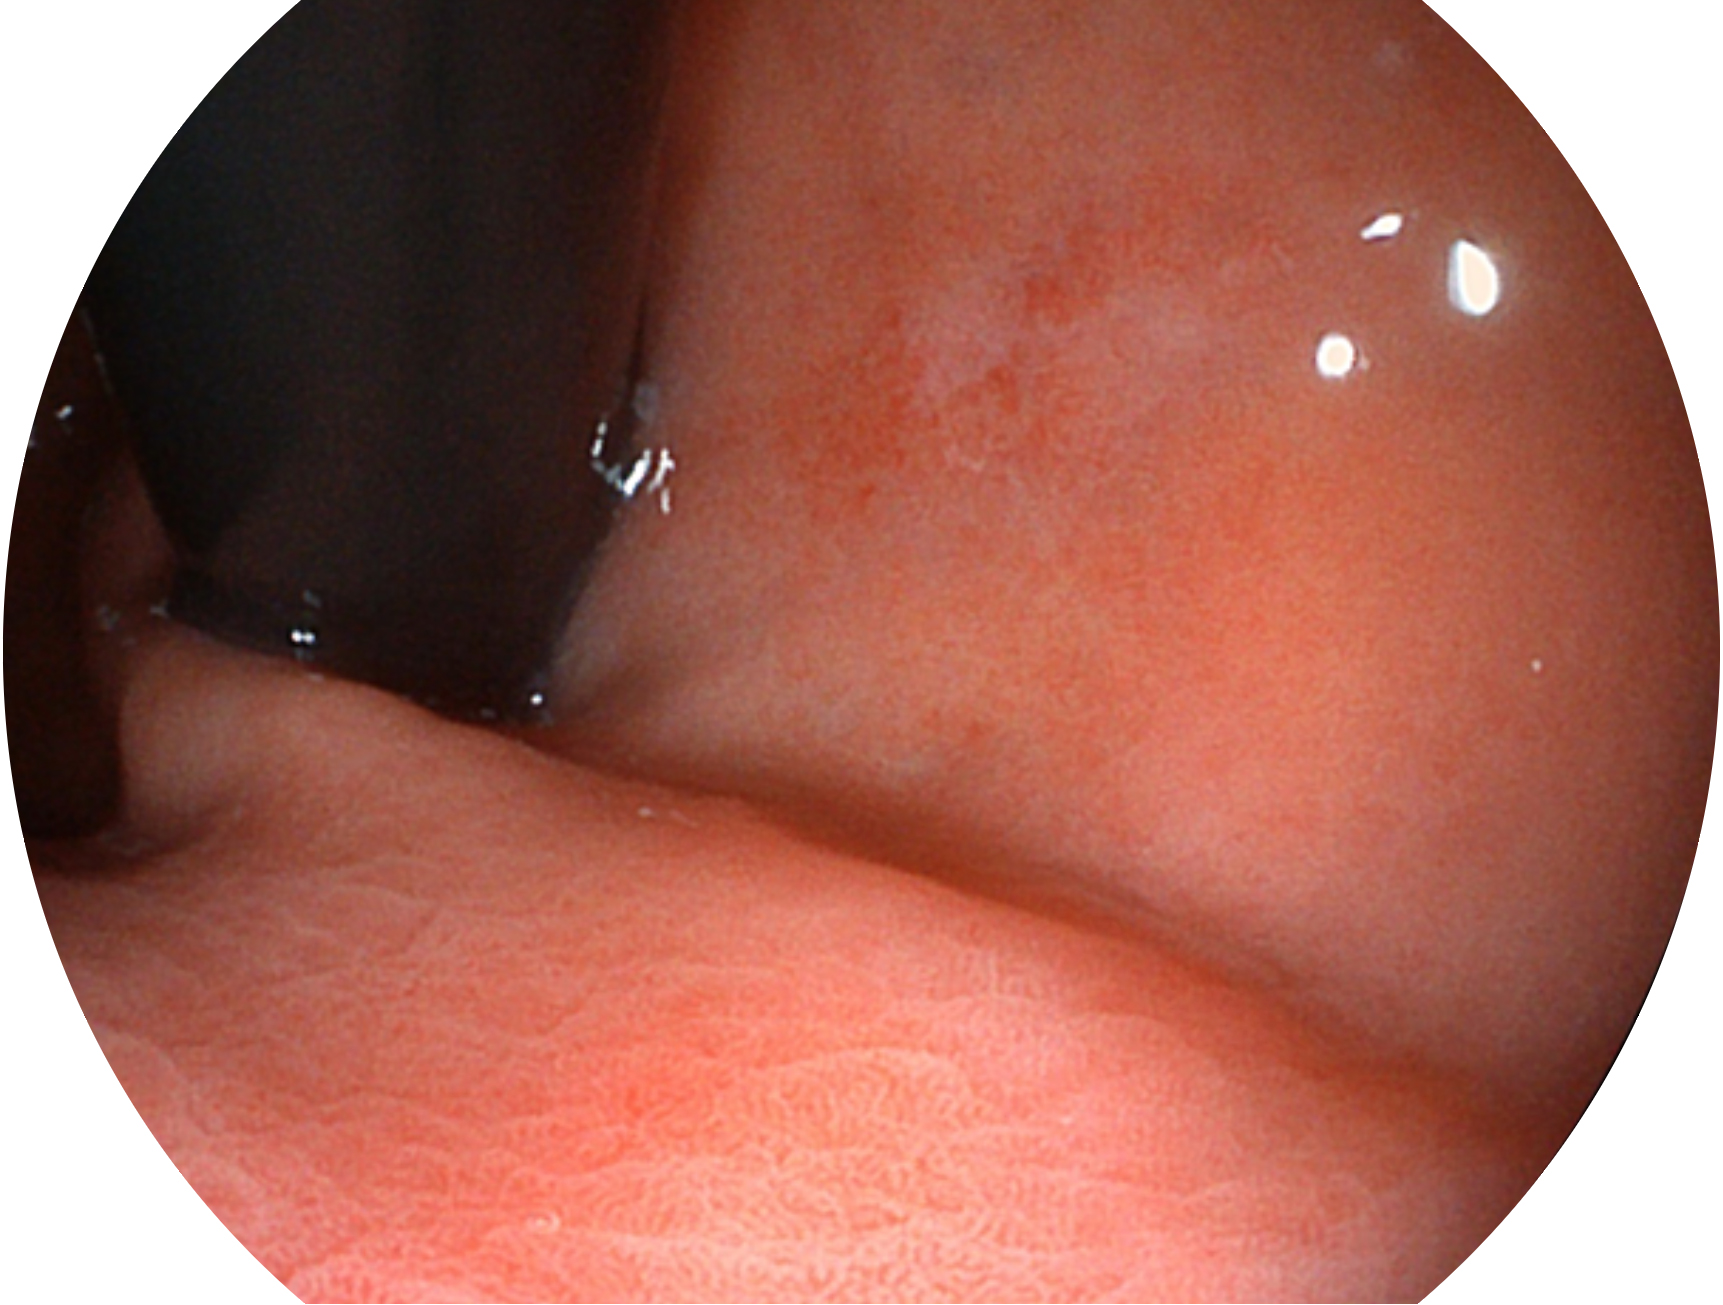

開立新開發(fā)的內(nèi)鏡染色技術(shù),主要是基于多波長LED 光源的開發(fā),VLS-55Q 四波長LED 光源是由四個不同顏色的LED光按照相應(yīng)照明模式所規(guī)定的特定發(fā)光比例進行合束后形成,合束后形成的照明光的光譜由紅光、綠光、藍光及藍紫光這四個不同的波段范圍構(gòu)成。具有更高光譜自由度,通過光譜比例的控制,實現(xiàn)了聚譜成像技術(shù),英文全稱為“Spectral Focused Imaging, SFI”,縮寫為“SFI”和光電復(fù)合染色成像技術(shù),英文全稱為“Versatile Intelligent Staining Technology, VIST”,縮寫為“VIST”。